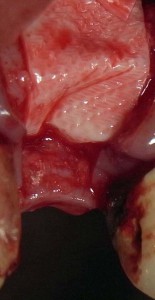

吸収性膜でカバー

吸収性膜でカバー